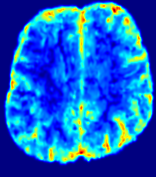

LesionRefer to captionRefer to captionRefer to captionRefer to captionRefer to captionRefer to caption𝐕rgbsubscript𝐕𝑟𝑔𝑏{\bf{V}}_{rgb}Refer to captionRefer to captionRefer to captionRefer to captionRefer to captionRefer to caption𝐕2subscriptnorm𝐕2{\|\bf{V}}\|_{2}Refer to captionRefer to captionRefer to captionRefer to captionRefer to captionRefer to captionRefer to caption3.53.53.52.82.82.82.12.12.11.41.41.40.70.70.70.00.00.0(mm/s)𝑚𝑚𝑠(mm/s)D𝐷DRefer to captionRefer to captionRefer to captionRefer to captionRefer to captionRefer to captionRefer to caption0.0200.0200.0200.0160.0160.0160.0120.0120.0120.0080.0080.0080.0040.0040.0040.0000.0000.000(mm2/s)𝑚superscript𝑚2𝑠(mm^{2}/s)Slice #1Slice #2Slice #3Slice #4Slice #5Slice #6

Figure 3: PIANO feature maps for one stroke patient, where the lesion is located in the left hemisphere. Top row: segmented stroke lesion region (white) on different slices, obtained from ISLES 2017. The corresponding slices for the PIANO feature maps are shown in the following rows.

For a better insight into an estimated velocity field 𝐕𝐕{\bf{V}} and diffusion field 𝐃𝐃{\bf{D}}, we compute the following maps: (1) 𝐕rgbsubscript𝐕𝑟𝑔𝑏{\bf{V}}_{rgb}: Color-coded orientation map of 𝐕=(Vx,Vy,Vz)T𝐕superscriptsuperscript𝑉𝑥superscript𝑉𝑦superscript𝑉𝑧𝑇{\bf{V}}=(V^{x},V^{y},V^{z})^{T}, obtained by normalizing 𝐕𝐕{\bf{V}} to unit length and mapping its 3 components to red, green, blue respectively; (2) 𝐕2subscriptnorm𝐕2\|{\bf{V}}\|_{2}: 222 norm of 𝐕𝐕{\bf{V}}; (3) D𝐷D: scalar field in Eq. 5.

Fig. 3 and Fig. 4 show the PIANO feature maps estimated from two ISLES 2017 patients: all are highly consistent with the lesion in both cases. Details of the blood flow trajectories are revealed in 𝐕rgbsubscript𝐕𝑟𝑔𝑏{\bf{V}}_{rgb} by the ridged patterns and the sharp changes of colors in the unaffected (right) hemisphere, while the flat patterns appearing within the lesion provide little directional information about the velocity and indicate low velocity magnitudes. Velocity magnitudes are more directly visualized via 𝐕2subscriptnorm𝐕2\|{\bf{V}}\|_{2}, from which one can easily locate the lesion where 𝐕2subscriptnorm𝐕2\|{\bf{V}}\|_{2} is low. D𝐷D also indicates lower diffusion values in the lesion, though with less contrast potentially due to the fact that it captures the accumulated effect of CA diffusion at the voxel-level.